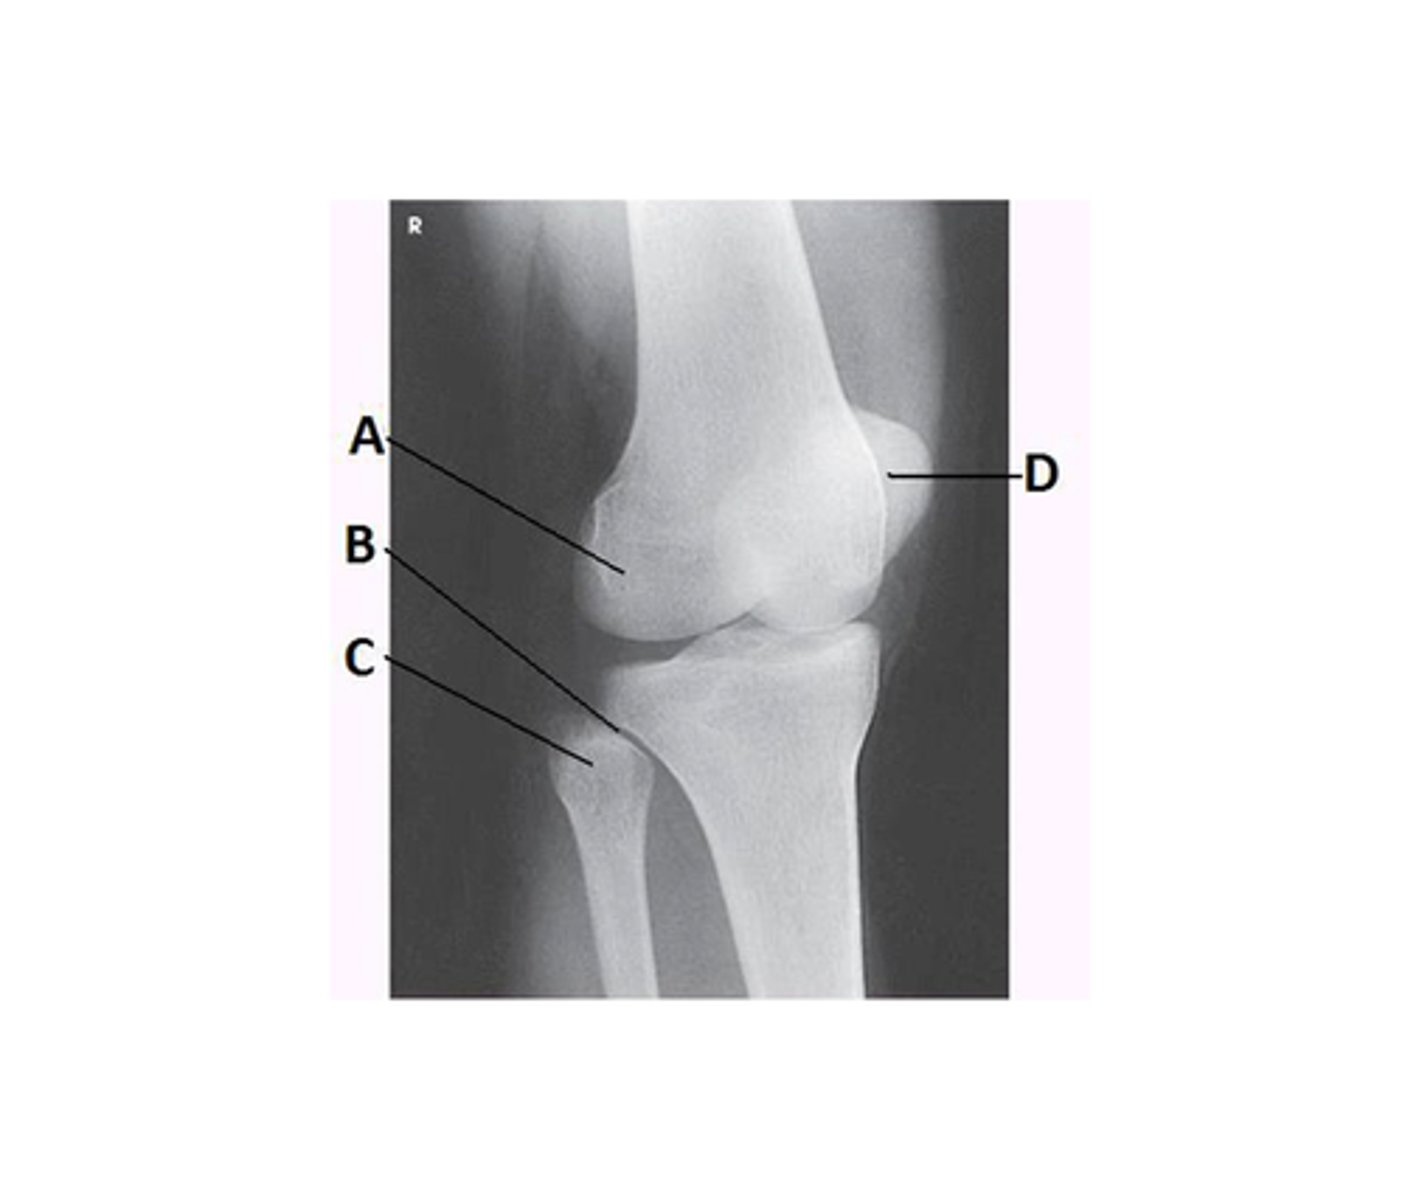

What anatomy is labeled with the letter B in the image below?

Proximal tibiofibular joint

What lower limb position is required to obtain the image below?

45-degree medial rotation